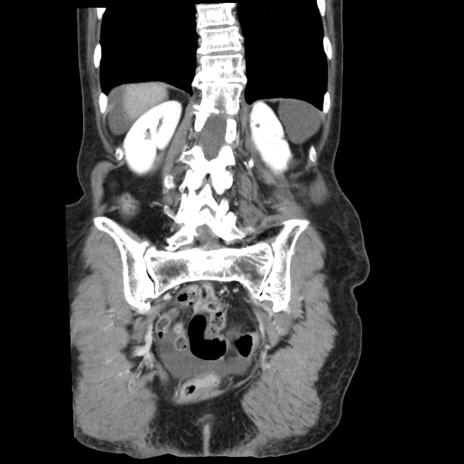

症例1(冠状断像)

【症例】80歳代女性

【主訴】腹痛

【現病歴】8時間前から腹痛あり来院。

【既往歴】糖尿病、脂質異常症、子宮体癌にて子宮全摘術

【身体所見】意識清明・会話良好だが腹痛で苦悶様、全腹部にわたって反跳痛と圧痛あり

【データ】WBC 13600、CRP 0.14、LDH 224、CK 90